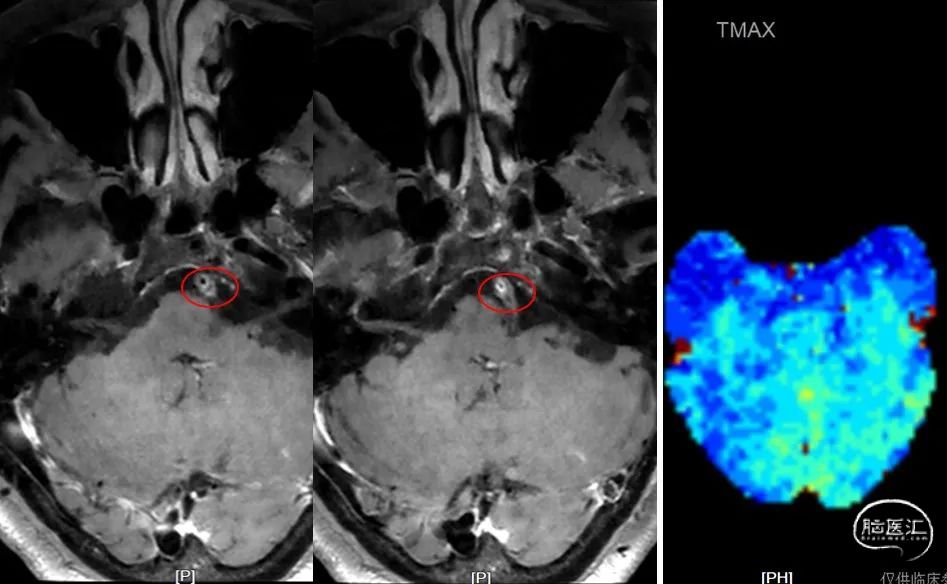

脑血管壁高清MR+灌注(2022-01-14):

高清血管壁

头颅灌注

高清血管MR示:双侧椎动脉颅内段及基底动脉近段管壁多发易损斑块形成,管腔重度狭窄,右侧椎动脉局部未见显示;PWI示:小脑及脑干灌注减低。